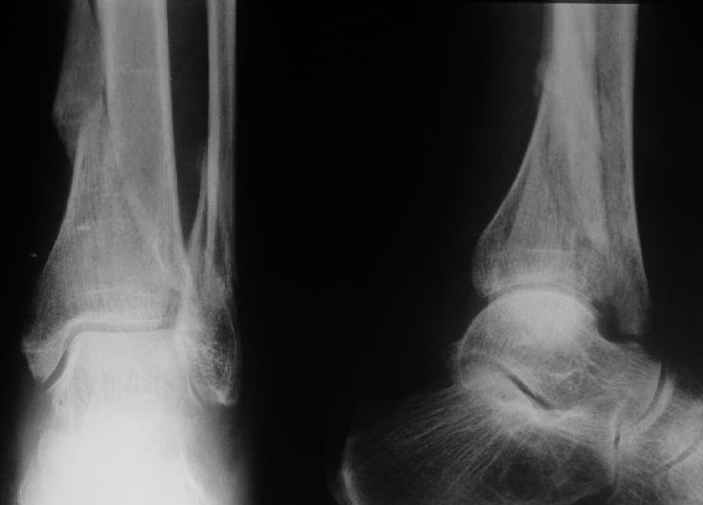

Дама 56 лет 6 недель назад получила спиральные переломы дистальных отделов костей голени. По месту жительства наложили гипс.

Сейчас вот, получается, спохватились. Снимки и КТ в приложении. Какой вариант тут предпочтительнее - открытая мобилизация, репозиция и внутренняя или наружная фиксация? Или ограничиться только резекцией костного шипа над шейкой тарана?Заранее спасибо.A female 56 y.o. 6 weeks ago sustained a fracture of the distal tibia/fibula. At the initial hospital a plaster cast was applied. Now she was referred to our unit. At the moment there is no pain, no obvious mobility. Images and CT attached.What is the best option here? Mobilize the fracture, perform open reduction and internal or external fixation? Or just to cut the anterior spike over the talar neck? THX in advance.

The anterior spike seems to be more antero-lateral, rather than anterior, in such a position that it may not hamper dorsiflexion.

The ankle mortise as a unit is intact.

Отправитель: Андрей 30 Август 2004, 00:44

Судя по рентгену, там вполне приличное сращение.Ось сохранена, укорочение - макс. 1,5 см. Чего ещё хотеть? Шип желатепьно убрать. Исключительно, чтобы

Though the upper tibia is not seen on the Xray and thus we cannot exactly see the amount of varus angulation, I presume it must be minimal and acceptable, otherwise you have noted and mentioned the same.